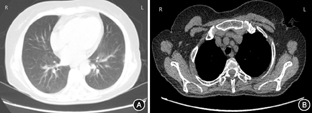

实验室检查:血红蛋白106 g/L(正常参考值:115~150 g/L),血肌酐170 μmol/L(正常参考值:44~115 μmol/L),血钙3.15 mmol/L(正常参考值:2.15~2.55 mmol/L),血管紧张素转化酶(ACE)173 U/L(正常参考值:0~52 U/L),红细胞沉降率37 mm/h(正常参考值:0~20 mm/h)、游离三碘甲状腺原氨酸2.29 pmol/L(正常参考值:2.63~5.70 pmol/L)。肝功能、腺苷脱氨酶、自身抗体谱未见异常,抗中性粒细胞胞质抗体(ANCA)、胞质型(c-ANCA)与核周型(p-ANCA)阴性,免疫球蛋白正常,免疫固定电泳未见单克隆条带。结核菌素(PPD)试验、结核分枝杆菌/利福平耐药检测(Xpert MTB/RIF)、1,3-β-D葡聚糖检测(G实验)、半乳糖甘露醇聚糖抗原检测(GM实验)、甲状旁腺素、甲状腺抗体、肿瘤全项、肺肿瘤标志物未见异常,人类免疫缺陷病毒、乙肝五项、丙肝抗体、梅毒阴性。尿潜血+-,尿蛋白+-,尿pH 6.00。尿N-乙酰-β-D-氨基葡萄糖苷酶62.8 U/g·Cr(正常参考值:1.1~12.0 U/g·Cr)、半乳糖苷酶32.5 U/g·Cr(正常参考值:2.0~14.0 U/g·Cr)。肾小管酸化功能:重碳酸盐31.90 mmol/L(正常参考值:0~12.44 mmol/L),可滴定酸4.10 mmol/L(正常参考值:9.57~150 mmol/L),铵离子14.40 mmol/L(正常参考值:25.84~200 mmol/L)。超声示双肾弥漫性病变。心电图、心脏超声未见明显异常。胸部CT示:双肺多发点片影,右肺中下叶及左肺下叶条索影,双肺间质纹理增多;少量心包积液(图1)。全身骨显像未见典型骨转移性病变图像。裂隙灯检查:双眼角膜后沉着物阳性,房水闪辉++,房水细胞++,玻璃体细胞++~+++,晶状体混浊。荧光造影:双眼视网膜血管炎、视盘荧光渗漏,黄斑区拱环斑驳状荧光。光学相干断层成像:双眼黄斑水肿。经眼科会诊后诊断为双眼全葡萄膜炎。左上肢皮下结节病理活检示:皮下脂肪上皮细胞肉芽肿,胶原纤维包绕,形成裸结节(图2)。结节病诊断成立。确诊后给予口服甲泼尼龙40 mg/d,泼尼松龙滴眼液0.1 ml/次,3次/d治疗2周,患者出院。出院后1年来门诊随访,口服甲泼尼龙逐渐减量至4 mg/d维持治疗,患者视物模糊较前好转,皮下结节较前缩小且部分消失,化验指标基本正常。

注:A:肺窗;B:纵隔窗。双肺多发点片影,右肺中下叶及左肺下叶条索影,双肺间质纹理增多;少量心包积液,纵隔内未见肿大淋巴结